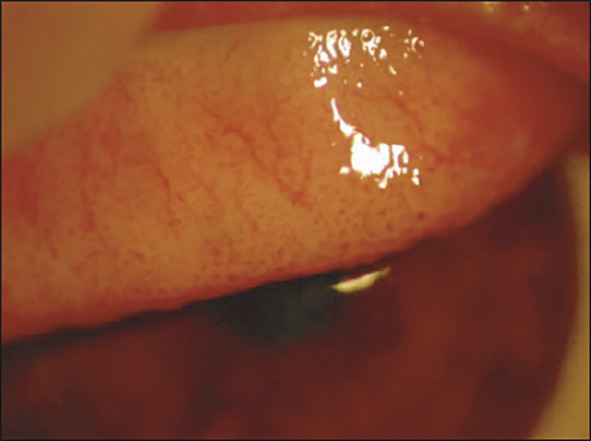

L’examen retrouve classiquement un chémosis majeur avec hyperhémie conjonctivale et une conjonctivite de type papillaire, plus ou moins associée à un œdème palpébral et des sécrétions muqueuses (fig. 1). À la différence de la kératoconjonctivite vernale (KCV), la cornée n’est pas atteinte. La résolution est souvent spontanée, en 24-48 heures.

L’examen à la lampe à fente révèle classiquement des papilles tarsales de taille moyenne : élevures framboisées centrées par un vaisseau, visibles lors de l’éversion des paupières supérieures. Les autres signes, communs avec la conjonctivite allergique aiguë, sont : inflammation conjonctivale avec hyper- hémie, œdème palpébral et secrétions muqueuses. La cornée n’est pas atteinte (fig. 2). Une rhinite est associée dans la majorité des cas. On parle de rhinoconjonctivite allergique.